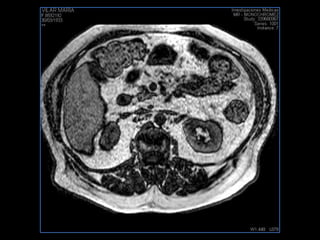

LIC ALEJANDRA GALVEZ RM DE ABDOMEN

PROTOCOLO abdomen COR T2, AXIAL supresion grasa AX T1 +SAG T2  CON   GADOLINIO :  COR T1+AX T1(DIN) SAT: NO  FASE: RL THK: 6MM  COIL:  GAP: (FACTOR 1.4) 2MM FOV: 40 CM NEX:2 SINCRONIZACION RESPIRATORIA EN 3 O 4 CICLOS ALE

resonancia de abdomen